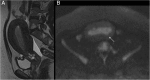

Endometrial cancer is the most common gynaecologic malignancy in developed countries and its incidence is increasing. First-level treatment, if no contraindicated, is based on surgery. Pre-operative imaging is needed for evaluation of local extent and detection of distant metastases in order to guide treatment planning. Radiological evaluation, based on transvaginal ultrasound, MR and CT, can make the difference in disease management, paying special attention to assessment of entity of myometrial invasion, cervical stromal extension, and assessment of lymph nodal involvement and distant metastases.